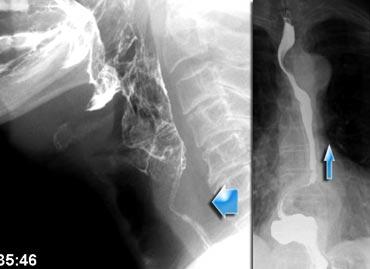

Nuốt bất đối xứng do xoay đầu. Đầu xoay sang trái và thuốc cản quang chỉ thấy ở kênh thức ăn bên phải.

Bất đối xứng

Nuốt bất đối xứng trên tư thế thẳng (AP) thường là kết quả của sự nghiêng không đều của nắp thanh quản.

Đôi khi nguyên nhân là do xoay đầu, nhưng trong nhiều trường hợp không tìm được giải thích thực sự.

Ngay cả khi đầu không xoay, nắp thanh quản vẫn có thể nghiêng bất đối xứng khi chạm vào thành hầu sau.

Điều này dễ xảy ra hơn khi chỉ cho một lượng bolus nhỏ, vì hầu họng sẽ không giãn nở hoàn toàn.

Một bolus lớn hơn sẽ tạo ra động tác nuốt đối xứng.

Trong trường hợp bên trái, việc xoay đầu sẽ đóng phía mà đầu xoay về (Hình).

Nếu bệnh nhân bị liệt hầu một bên, việc xoay đầu về phía bên bị tổn thương sẽ giúp bệnh nhân phòng ngừa hít sặc.

Bằng cách xoay đầu về phía bên bị tổn thương, phía này sẽ bị đóng lại, ngăn ngừa ứ đọng ở phía này và khả năng hít sặc thứ phát.

Tuy nhiên, trước khi kết luận đây là dấu hiệu bình thường, cần loại trừ khối u hầu họng hoặc liệt một bên.

Hình ảnh đối quang kép có thể hữu ích trong những trường hợp này.

Trong liệt một bên, phía bị liệt sẽ phồng ra trong nghiệm pháp Valsalva cải tiến.

Khi có khối u trong hầu họng, thường có thể thấy trên hình ảnh đối quang kép.

Đôi khi cần nội soi để giải quyết vấn đề nuốt bất đối xứng.

Bất đối xứng (2)

Trường hợp bên trái là một ca bệnh đặc biệt, nhưng minh họa rõ nét sự khó khăn đôi khi gặp phải trong việc xác định nguyên nhân gây bất đối xứng.

Ở hình ngoài cùng bên trái, bất đối xứng được thấy trên nghiên cứu huỳnh quang (mũi tên xanh lá).

Có vẻ như có gì đó trong xoang lê bên phải.

Trên hình ảnh đối quang kép bên phải, xoang lê bình thường (mũi tên xanh lá), nhưng ở mức thung lũng nắp thanh quản bên phải thấy một tổn thương dạng thùy (mũi tên vàng).

Ở mức cao hơn, thấy một vết lõm nhẵn của hầu miệng (mũi tên xanh dương).